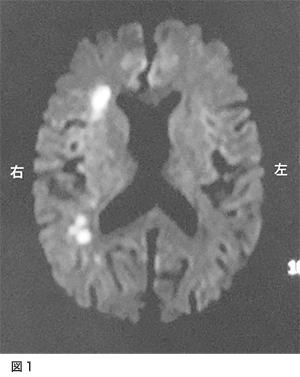

脳梗塞で発症された方です。意識障害と左不全片麻痺、構音障害で発症されました。図1が入院時のMRI拡散強調画像です。右側の白くなっているところが脳梗塞になっている部位です。図2の、MRA(MRIで行う血管の検査)では、右側の中大脳動脈の描出がほとんど無い状態でした。